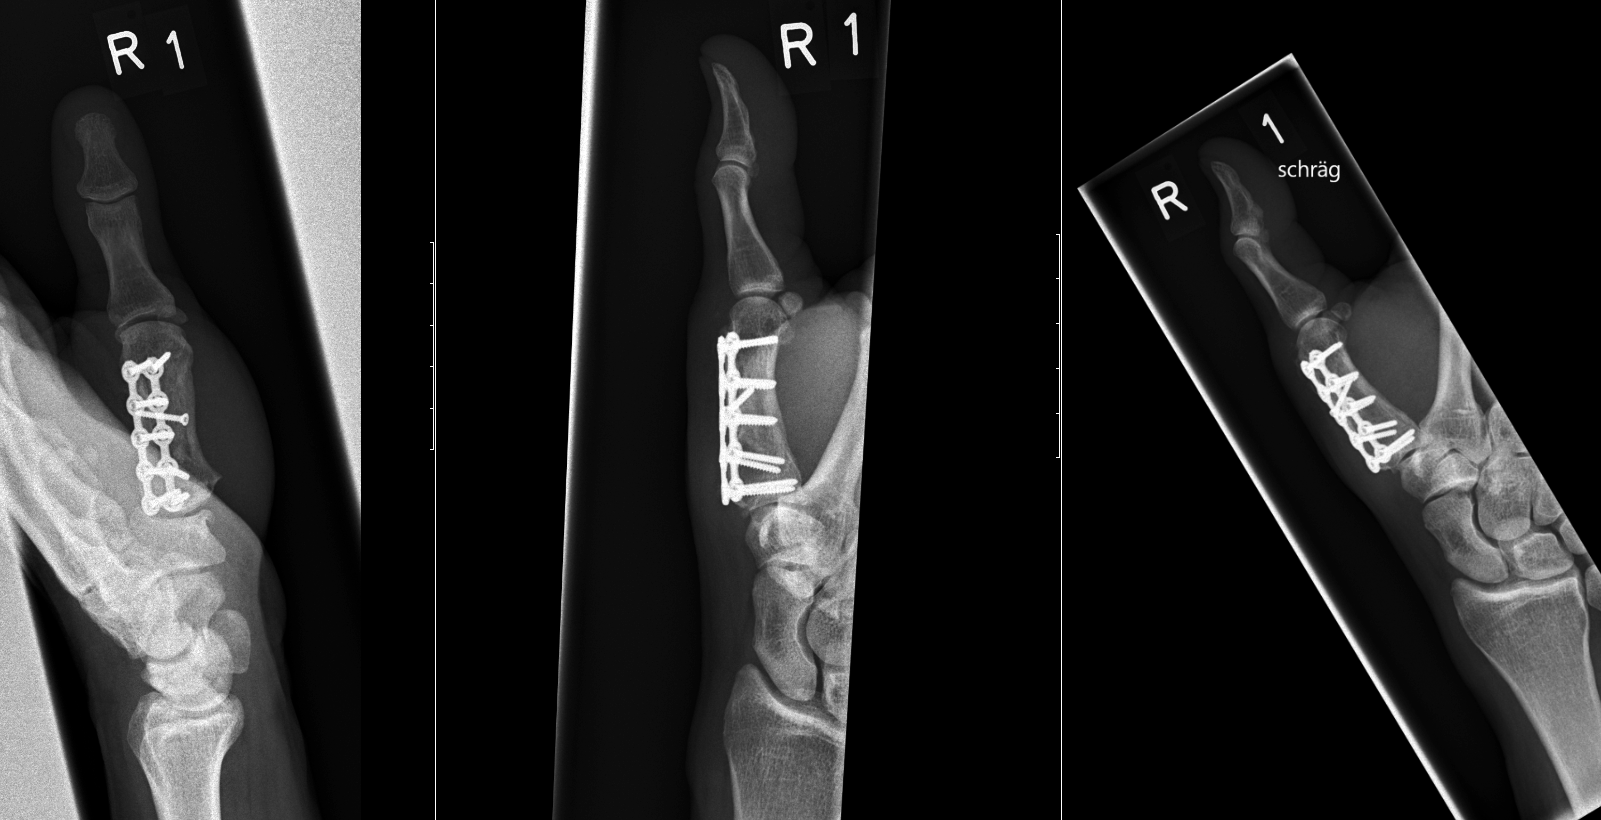

Case 2:

A 20-year-old male suffered a complex multi-digit injury of the right hand requiring revascularization and stabilization of both proximal phalanx and PIP joint fractures (Figs 5 - 8). Multiple plates, including the rotation correction plate from the 1.5 module of the VA Locking Hand System were used for fixation. The Variable Angle Locking system is ideal when only two screws, either proximal or distal, are able to be inserted due to space limitation.

One major advantage of variable angle technology in very distal phalangeal fractures is the ability to be extremely flexible with a wide range of fixation options. Freedom of implant placement assists early mobilization, vital in these complex fractures with associated soft-tissue trauma.